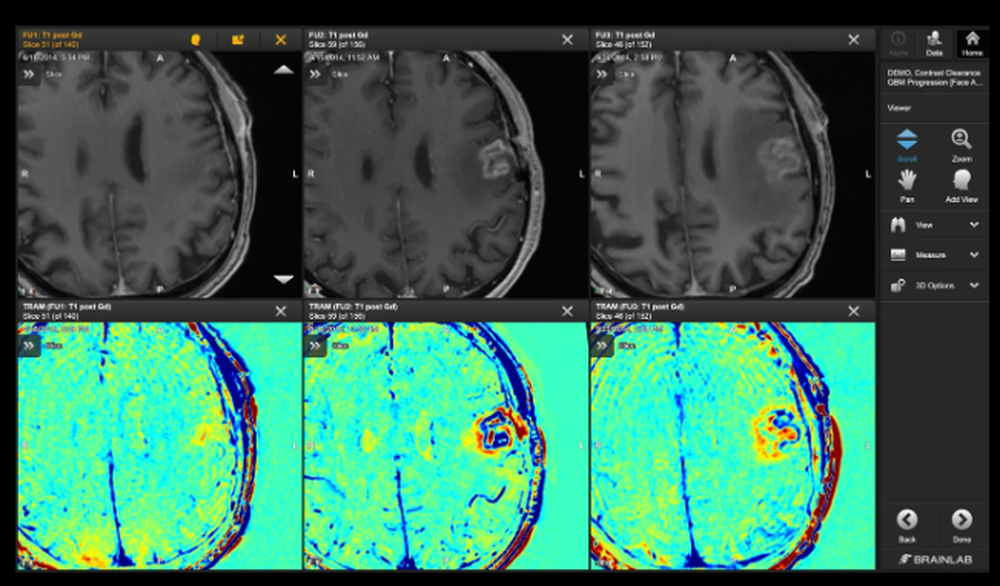

Brainlab's Elements Contrast Clearance Analysis is an MRI-based technique aimed at distinguishing areas of contrast clearance and accumulation within brain tumor imaging datasets. This advanced high-resolution analysis enhances the understanding required for ongoing evaluations and decision-making across various clinical fields, including radiosurgery, radiation oncology, neurosurgery, neuro-oncology, and neuroradiology. The methodology entails capturing two standard 3D T1-weighted MRIs; the first scan is taken around 5 minutes after administering a standard dose of contrast agent, while the second scan occurs 60 to 105 minutes later. By subtracting the initial series from the subsequent one, volumetric maps are created that clearly identify zones of contrast clearance (shown in blue) against those of contrast accumulation (illustrated in red). These findings empower clinicians to better evaluate the effects of radiation treatment in contrast to potential tumor regrowth, allowing for more educated decisions regarding both initial and subsequent treatment plans. As a result, this analysis not only aids in clinical assessments but also enhances the overall management of patient care in complex cases.

Elements Contrast Clearance Analysis Screenshot 1